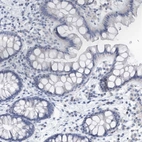

Immunohistochemistry analysis in human adrenal gland and colon tissues using Anti-VWA5B2 antibody. Corresponding VWA5B2 RNA-seq data are presented for the same tissues.